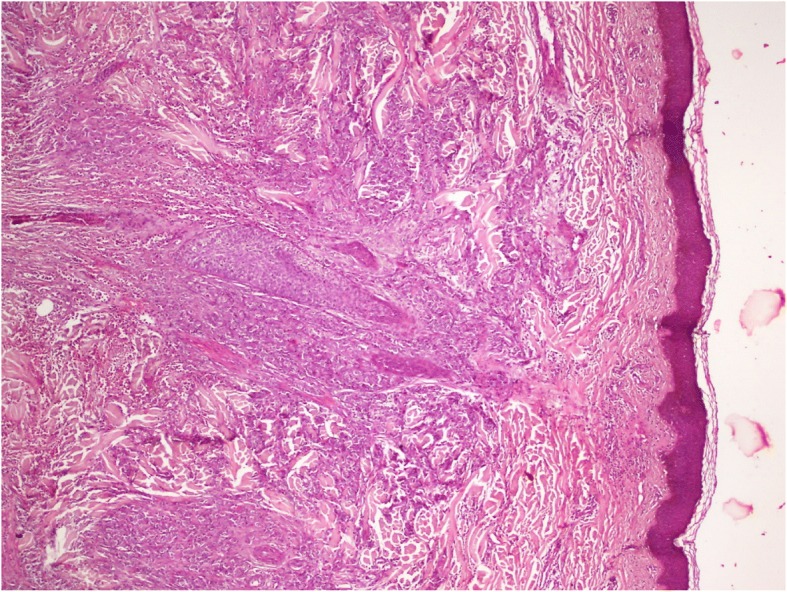

The patient had a biopsy of the left hypochondriac lesion (Fig. 4), and the histology confirmed the metastatic origin. The tumor was CK7- and P63-positive (Figs. 5, 6 and 7).

Fig. 5.

H&E coloration showing the tumoral proliferation under the skin layer

Concerning histology, cutaneous metastases predominantly involve the dermis, and there is usually a narrow zone of superficial dermis separating the lesion from the epidermis [2]. That is why some authors recommend excisional or punch biopsy rather than superficial shaving biopsy [2].